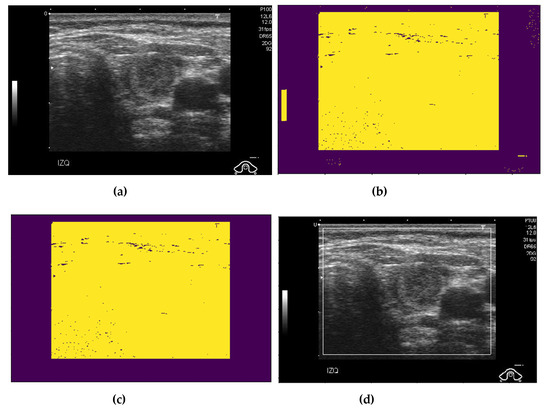

2.2. Preprocessing of Captured Thyroid Images